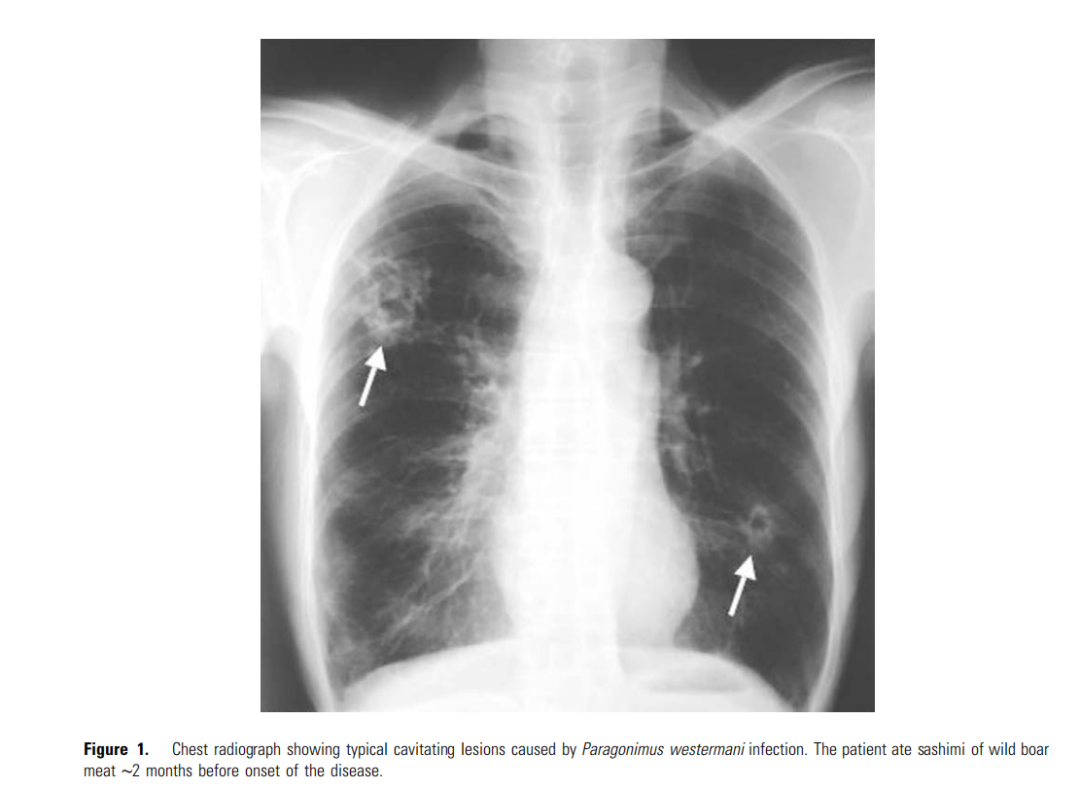

一位吃了生鱼片后,感染肺吸虫的病患。放射图中箭头所指的即肺吸虫造成的病灶